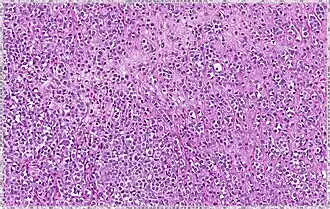

| Solid | 10% | Sheets of classical-appearing cells with little intervening stroma | |

| Alveolar | 5% | Aggregates of classical-appearing cells | |

| Tubulolobular | 5% | Cells form microtubules in >90% of tumor (smaller than in tubular carcinoma) | |

| Pleomorphic | Classical-appearing but with pleomorphic cells. It may include signet-ring cells, or plasmacytoid cells (pictured) which have abundant cytoplasm and eccentric nuclei. | ![]() |

Histopathology of invasive lobular carcinoma (ILC), next to lobular carcinoma in situ (LCIS) -

Invasive lobular carcinoma demonstrating a predominantly lobular growth pattern -

Lobular breast cancer. Single file cells and cell nests. -

ILC may be subtle on low magnification (left). Higher magnification (right) shows invasive growth pattern and vesicular nuclei with prominent nucleoli.